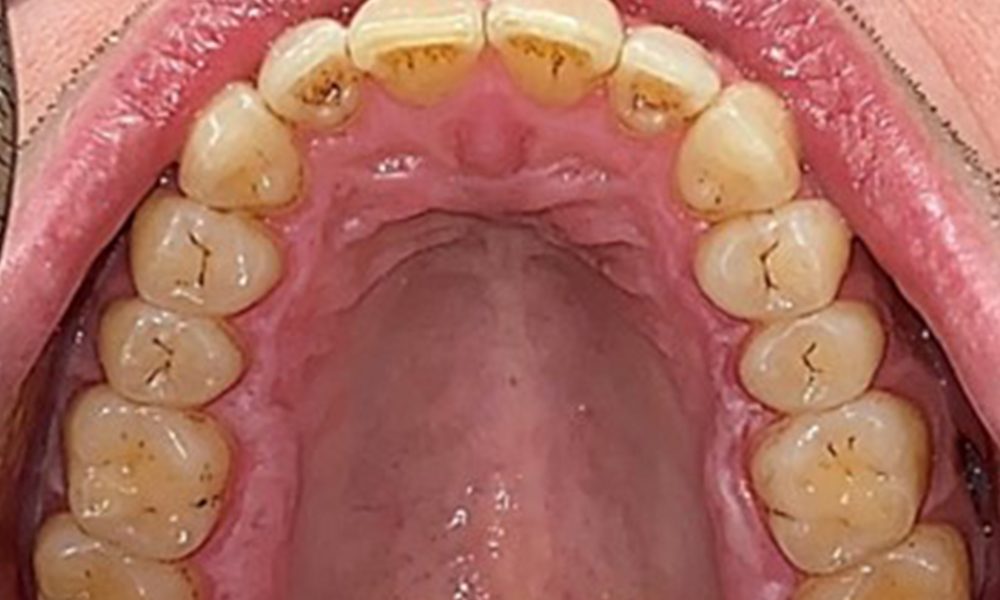

The patient has full dentition with a total of 28 teeth. There were noteworthy erosions and attritions. (Fig. 4, Fig. 5). Due to bruxism, the patient has been wearing a splint with an adjusted bite block at night for many years. The erosions were caused by long-term consumption of isotonic beverages. No periodontal bone loss or active caries were observed.

Full complement of adult teeth with no caries or radiologically recognizable bone loss was observed (Fig. 6). Radiological enamel and cusp loss were particularly evident on 36 and 37.